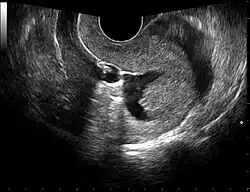

The examination can be performed by transabdominal ultrasonography, generally with a full bladder which acts as an acoustic window to achieve better visualization of pelvis organs, or by transvaginal ultrasonography with a specifically designed vaginal transducer. Transvaginal imaging utilizes a higher frequency imaging, which gives better resolution of the ovaries, uterus and endometrium (the fallopian tubes are generally not seen unless distended), but is limited to depth of image penetration, whereas larger lesions reaching into the abdomen are better seen transabdominally. Having a full bladder for the transabdominal portion of the exam is helpful because sound travels through fluid with less attenuation to better visualize the uterus and ovaries which lies posteriorly to the bladder. The procedure is by definition invasive when performed transvaginally. Scans are performed by health care professionals called sonographers, or gynecologists trained in ultrasound.

Through transvaginal sonography ovarian cysts can be aspirated. This technique is also used in transvaginal oocyte retrieval to obtain human eggs (oocytes) through sonographic directed transvaginal puncture of ovarian follicles in IVF.